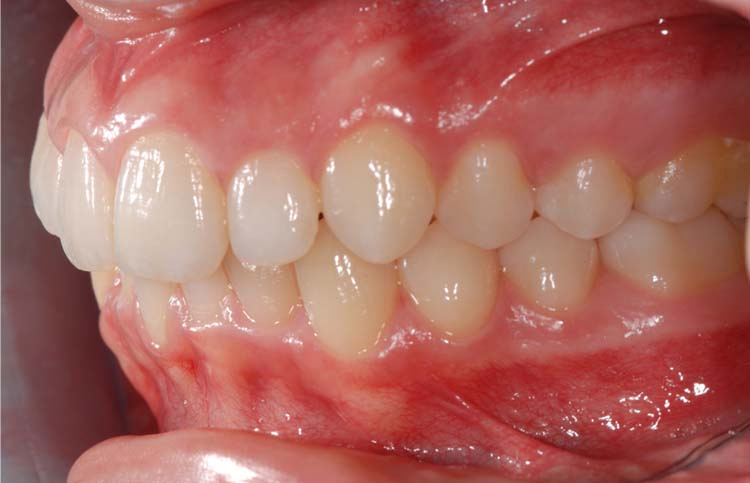

Caso clinico 1

Caso clinico 2

Caso clinico 3

Caso clinico 4

Caso clinico 5

Caso clinico 6